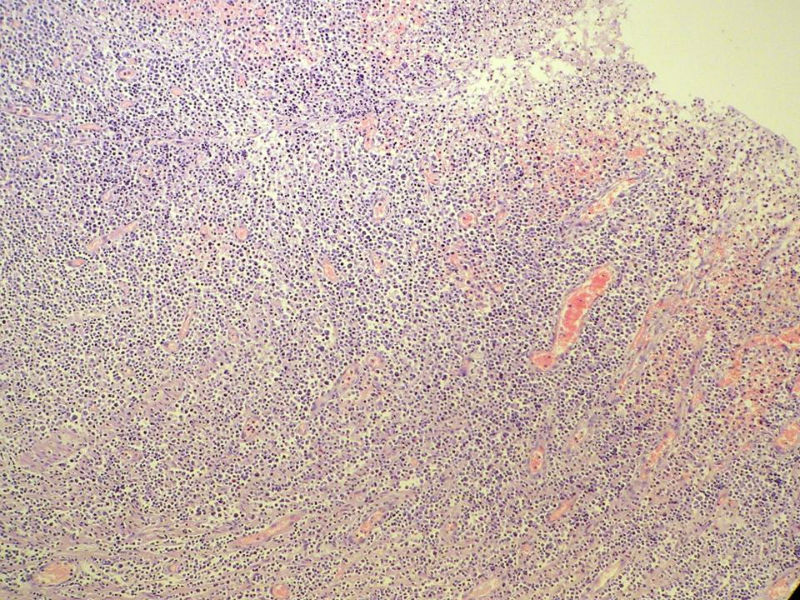

女,53岁,横结肠有9X6厘米大小溃疡,手术切除。

中老年人,溃疡很大,可见淋巴浆细胞样细胞弥漫浸润,散在大细胞,疑非霍奇颈淋巴瘤,倾向MALT伴浆样分化,不知是否破坏肌层?可否传肌层图?需IHC标记,鉴别淋巴瘤、腺癌及其它。

肉眼观仅是溃疡?有没有肠壁增厚、隆起?周围粘膜情况?肌层情况?有淋巴浆细胞样细胞、中心细胞,散在少量不成片的大细胞,不排除MALToma伴大细胞转化。

本例肉眼溃疡如溃疡性结肠炎,肠壁无明显增厚,表面辅以坏死,溃疡边缘稍隆起。镜下淋巴样细胞局限在粘膜层,肌层未见。谢谢!